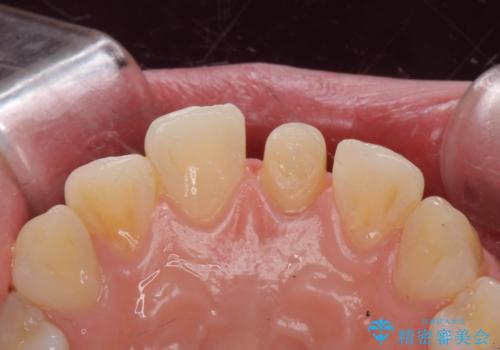

前歯の変色とガタつき ジルコニアクラウンでの修復

- 前歯の変色とガタつきが気になるとのことで来院された患者様です。

根管治療からやり直しを行った後、ジルコニアクラウンで修復することで、ガタつきと変色の両方を改善していきます。

ガタつきと変色の両方を改善することができ、大変喜んでいただけました。

少しのガタつきであれば、矯正治療を行わなくても改善できる場合があります。